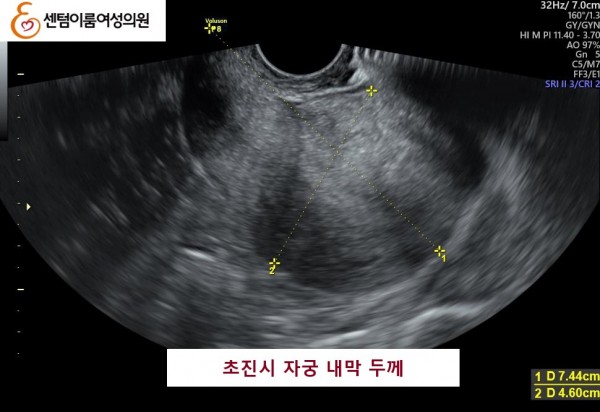

2025.4월 본원 내원 전 타병원에서 시술 받으신 경험이 있으셨습니다.

40세 이상 고령 연령은 염색체 비정상 난자 비율이 높아 고난도 난임의 대표적인 사례입니다.

꾸준한 식생활 개선과 약물 치료후, 시술로 쌍둥이 임신에 성공 하셨습니다.